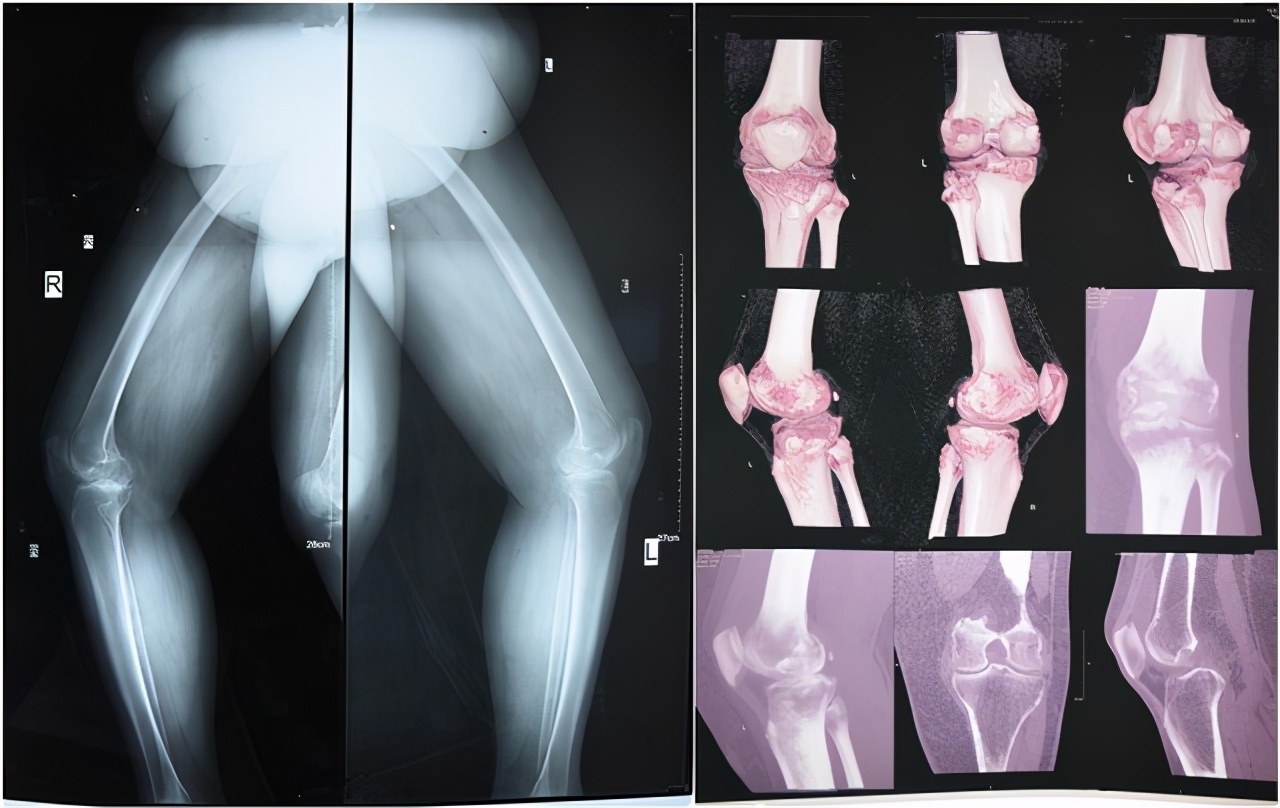

入院查体示:左、右膝部轻微肿胀,局部皮温正常,双膝关节周围轻微压痛,浮髌试验阴性,髌骨研磨试验可疑阳性,前后抽屉试验阴性,左、右膝关节活动度受限,右膝伸20度,屈95度,左膝伸15度,屈100度。

(术前检查)

影像检查:

1、MRI提示;双侧膝关节退行性改变,双侧股骨内外侧髁及胫骨平台软骨变性伴关节面下囊变;双膝关节内外侧半月板前后角变性;双膝关节腔积液,以髌上囊严重。

2、CT提示;双侧膝关节退行性病变,双膝关节腔积液。

3、DR提示;双膝关节退行性骨关节炎。

结合病史体征及辅助检查初步诊断为双膝关节骨性关节炎,经外二科医生团队讨论及评估,认为患者双膝关节骨性关节炎严重,建议双侧使用人工膝关节代替已经病变的膝关节,从而缓解膝关节疼痛,改善膝关节功能,提高生活质量。